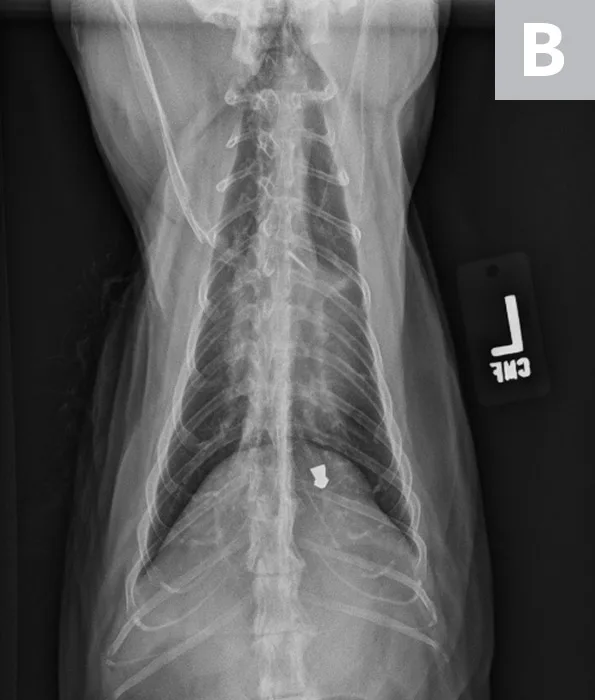

VHS calculation in a cat diagnosed with HCM using a right lateral radiograph (A). L (ie, long axis; 5.0) is drawn from the carina to the most ventral aspect of the apex. S (ie, short axis; 3.5) is drawn perpendicular to L at the widest aspect of the heart, extending to the cranial and caudal borders. S and L are transposed along the spine from the cranial aspect of T4 using calipers. The number of vertebrae traversed (rounded to the nearest tenth) are summed to calculate VHS (8.5). Pulmonary vasculature is prominent but within normal limits, and there is a ballistic metallic foreign body (likely a bullet) in the dorsal subcutaneous tissue of the caudal thorax. Moderate spondylosis deformans exists at T13-L1 and L1-L2, and there is bridging spondylosis deformans at T10-T11. Intervertebral disk space at T10-T11 is collapsed, and there is fusion at the 2 vertebral bodies. Orthogonal radiograph of the patient is also shown for more complete evaluation of cardiac silhouette (B).

A 12-year-old neutered male domestic shorthair cat was presented for evaluation of a previously diagnosed heart murmur. On physical examination, a grade III-IV/VI left parasternal systolic murmur was auscultated. All other physical examination findings were within normal limits. There is history of right thoracic limb lameness and mild lytic lesions on the right humerus. Thoracic radiographs revealed mild to moderate cardiac silhouette enlargement with VHS 8.5, suggestive of cardiac disease (Figure 2). Additional cardiac diagnostic investigation (eg, total thyroxine, echocardiography) is recommended, and medical treatment should be considered.